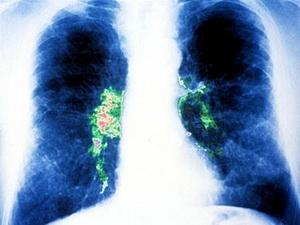

Trong năm 2013, một số tiến bộ Y học có thể sẽ được thị trường hóa và một số sẽ tiếp tục được thử nghiệm, đem lại nhiều hi vọng cho nhân loại. Dưới đây là những thành tựu Y học được mong đợi nhất năm nay. Chi tiết »